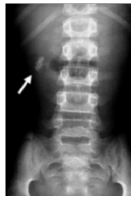

A radiografia simples de abdome acima evidencia imagens radiopacas no hipocôndrio direito caracterizando: